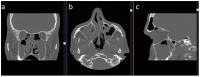

(1) Background: Computed tomography (CT) is considered mandatory for assessing the extent of pathologies in the paranasal sinuses (PNS) in chronic rhinosinusitis (CRS). However, there are few evidence-based data on the value of ultrasound (US) in CRS. This multicenter approach aimed to compare diagnostic imaging modalities in relation to findings during surgery. (2) Methods: 127 patients with CRS were included in this prospective multicenter study. Patients received preoperative US and CT scans. The sensitivity and specificity of CT and US were extrapolated from intraoperative data. (3) Results: CT scans showed the highest sensitivity (97%) and specificity (67%) in assessing CRS. Sensitivities of B-scan US were significantly lower regarding the maxillary sinus (88%), the ethmoid sinus (53%), and the frontal sinus (45%). The highest overall sensitivity was observed for assessing the pathology of the maxillary sinus. (4) Conclusions: We observed high accuracy with CT, confirming its importance in preoperative imaging in CRS. Despite the high US expertise of all investigators and a standardized examination protocol, the validity of CT was significantly higher than US. Ultrasound of the PNS sinuses is applicable in everyday clinical practice but lacks diagnostic accuracy. Nevertheless, it might serve as a complementary hands-on screening tool to directly correlate the clinical findings in patients with PNS disease.